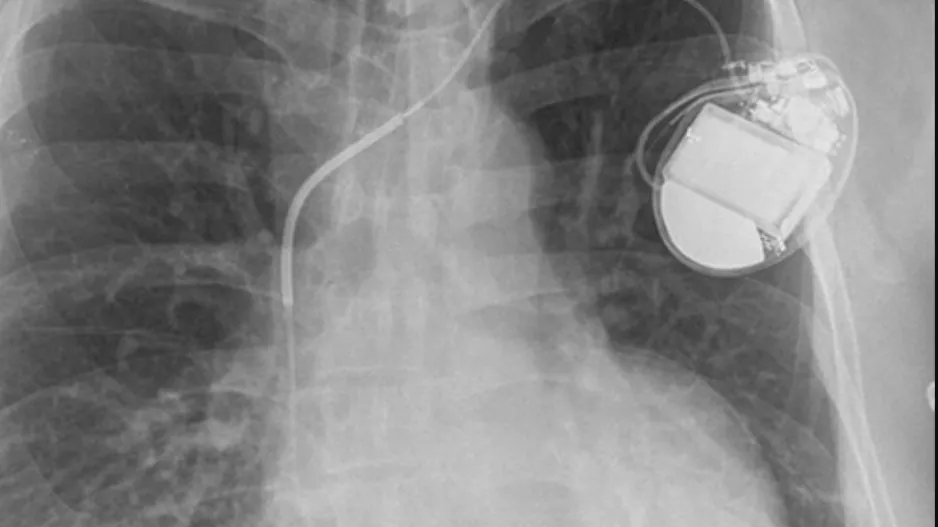

The U.S. Food and Drug Administration (FDA) has approved Abbott’s Aveir single-chamber (VR) leadless pacemaker as a treatment option for patients with slow heart rhythms. It is the second VR leadless pacemaker to gain approval in the…